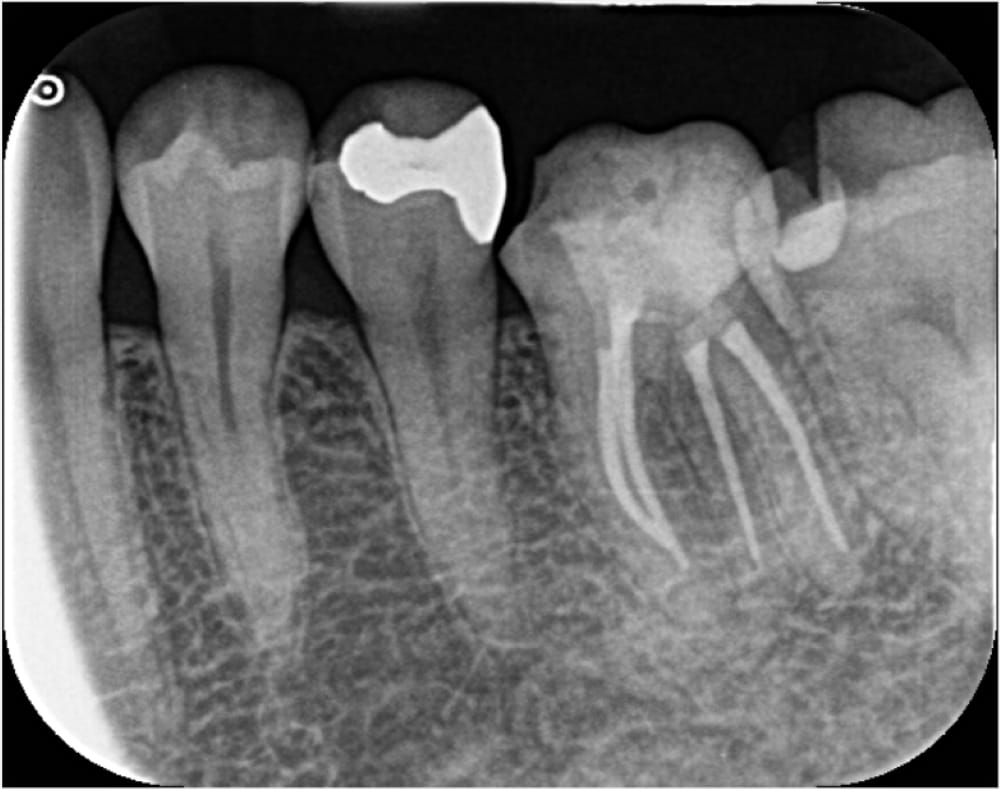

12ヶ月後の経過観察

12ヶ月経過時には、日常生活でほとんど気にならないレベルにまで症状は軽減しました(たまに違和感を感じる程度)。患者様にも、おそらくこれ以上感覚は戻らないことをお伝えしたところ、問題ないとのことで、仮歯装着後、最終補綴(クラウン)へ移行しました。

クラウン作製・装着

根管治療後、ジルコニアによるクラウンを装着しました。

かぶせものの適合や咬合にも問題はなく、治療は完了しました。